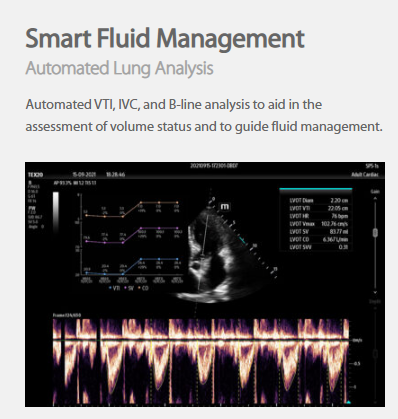

The technology-rich TE X Ultrasound System gives clinicians access to market-leading artificial intelligence (AI)-powered Smart Tools, an ergonomically designed system, and proprietary software-based beamformer Zone Sonography Technology+ (ZST+). By incorporating these elements, the TE X Ultrasound System provides access to advanced diagnostic data, the ability to adapt to the various clinical scenarios at point of care, and best-in-class imaging to help them provide a higher standard of care.